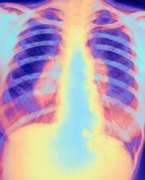

Странам ЕС угрожает новая опасность – устойчивый к лекарственным препаратам туберкулез. С таким заявлением выступили представители ВОЗ.

Согласно статистике ВОЗ, проблема лекарственной устойчивости микобактерий туберкулеза наиболее остро стоит в странах бывшего СССР (включая, к сожалению, Россию), а также в странах Восточной Европы, где доля случаев устойчивого туберкулеза достигает 14 процентов. На втором месте стоят Южная Африка, Израиль и некоторые районы Китая. Причем для современного резистентного туберкулеза характерно явление, называемое «суперрезистентностью» - то есть устойчивость не к одному классу противотуберкулезных препаратов, а к 3-4 – оно встречается в 80 процентах случаев.